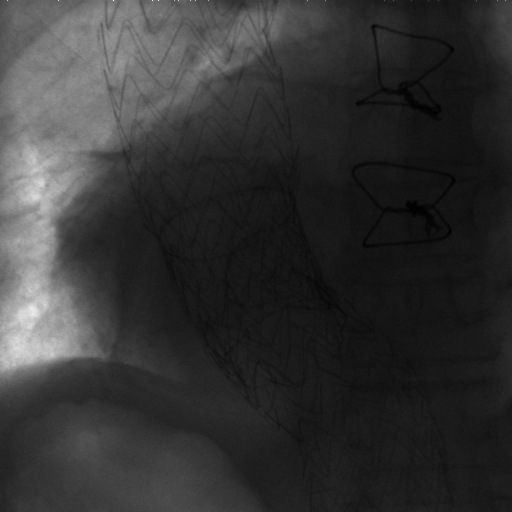

The dataset we use in the experiments is a cone-beam CT (CBCT) dataset captured for radiation therapy. The dataset contains 340 raw CBCT scans with each has 780 X-ray images. Each X-ray image comes with a geometry file that provides the registration ground truth as well as the information to reconstruct the CBCT volume. Each CBCT volume is reconstructed from the 780 X-ray images, and in total, we have 340 CBCT volumes (one for each CBCT scan). We use 300 scans for training and validation, and 40 scans for testing. The size of the CBCT volumes is 448×448×768448448768448\times 448\times 768 with 0.5 mm voxel spacing, and the size of the X-ray images is 512×512512512512\times 512 with 0.388 mm pixel spacing. During the experiments, the CBCT volumes are treated as the 3D pre-intervention data, and the corresponding X-ray images are treated as the 2D intra-intervention data. Sample X-ray images from our dataset are shown in Figure. Note that unlike many existing approaches [15, 17, 25] that evaluate their methods on small datasets (typically about 10 scans) which are captured under relatively ideal scenarios, we use a significantly larger dataset with complex clinical settings, e.g., diverse field-of-views, surgical instruments/implants, various image contrast and quality, etc.

Refer to caption

Figure 6: Sample raw X-ray images of our dataset.